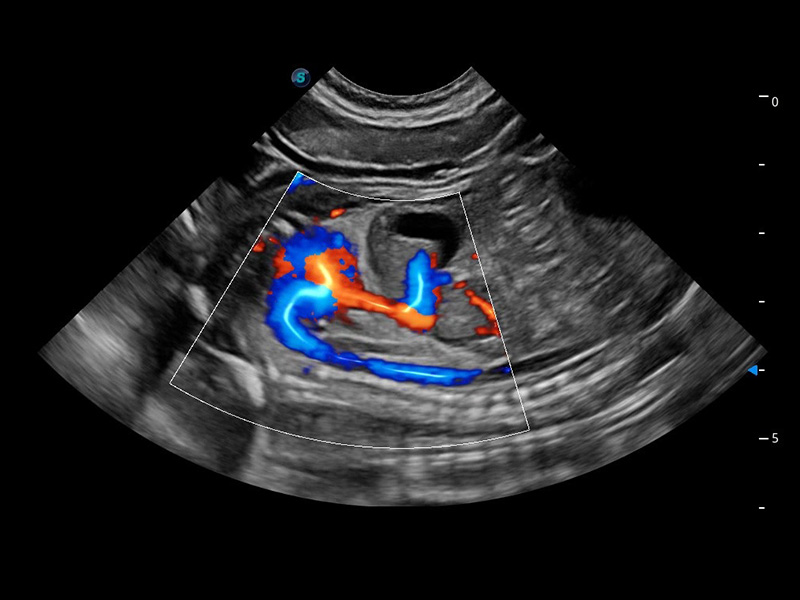

(犬)四腔心血流

4T血流成像 微察秋毫

融合不同血流成像技术的优势,即可以提升血流成束性,同时可提高血流的视觉敏感性。

Bright Flow 立体血流成像

在传统二维血流成像的基础上,呈现血流的立体感,具有动感的生命力之美。精确区分不同血管的空间关系,提高了血流的视觉敏感性。